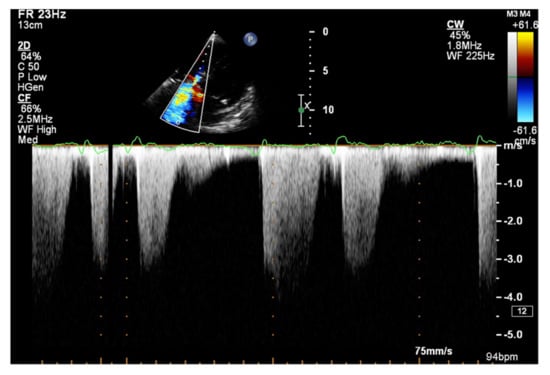

The dP/dt parameter, an indicator of the rate of pressure rise during the systolic phase in the RV, has a documented value in assessing RV systolic function [49]. To measure the dP/dt parameter, it is necessary to visualize a clear contour of the tricuspid return wave using the continuous wave Doppler (CWD). Singbal et al. showed that the dP/dt ratio correlates strongly with RVEF measured by CMR. Values of dP/dt below 400 mmHg/s were consistent with reduced RVEF [50]. In addition, decreased dP/dt is a significant TAPSE-independent marker of an adverse course of PAH and CTEPH [51].

It is believed that if there is no RV outflow tract stenosis, the right ventricular systolic pressure (RVSP) is equal to the pulmonary artery systolic pressure (PASP) [70]. In everyday practice, the calculation of PASP is based on a simplified Bernoulli equation applied to peak tricuspid regurgitation velocity (TRV). TRV should be measured in several views, aiming at the best image quality and maximum velocity in continuous-wave Doppler and avoiding excessive gain and artifacts (Figure 12 and Figure 13). According to the equation, PASP = 4 (TRV)2 + RAP [71,72]. In addition, based on the measurements of end-diastolic pulmonary regurgitant return wave velocity (PRVend), it is possible to estimate pulmonary artery diastolic pressure (PADP) using the PADP = 4 (PRVend)2 + RAP formula [73]. On the other hand, PASP and PADP values can be used to calculate approximations of mean pulmonary artery pressure (mPAP) using the mPAP = 1/3 (PASP) + 2/3 (PADP) formula [74]. Several other formulas for calculating mPAP can be found in the literature. Chemla et al. developed another method to calculate mPAP, according to the formula mPAP = 0.61 × PASP + 2 mmHg [75].

Figure 12.

Doppler assessment of tricuspid regurgitant velocity (TRV). TTE, 4CH view. TTE: transthoracic echocardiography; 4CH: four-chamber.